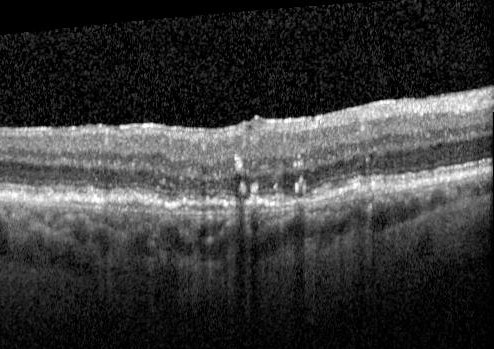

Pigment migration in dry age-related macular degeneration

80 year old female. Dry AMD with GA in the left eye and pigment migration visible on OCT scan.

VA 20/40 OD, 20/160 OS